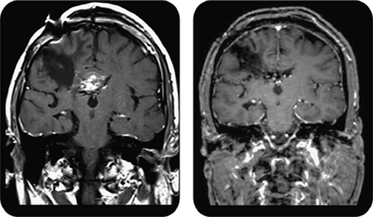

Everolimus室巨细胞星形细胞瘤的长期安全性和有效性嵌入式图像

嵌入式图像

25室巨细胞星形细胞瘤患者口服everolimus起价3毫克/米2每天和滴定,耐受性,达到全血槽浓度的5 - 15 ng / mL。利益相关的疾病肾肿瘤和面部血管纤维瘤。哺乳动物雷帕霉素靶抑制剂是一种有效的治疗结节性硬化症。

看到p。574年